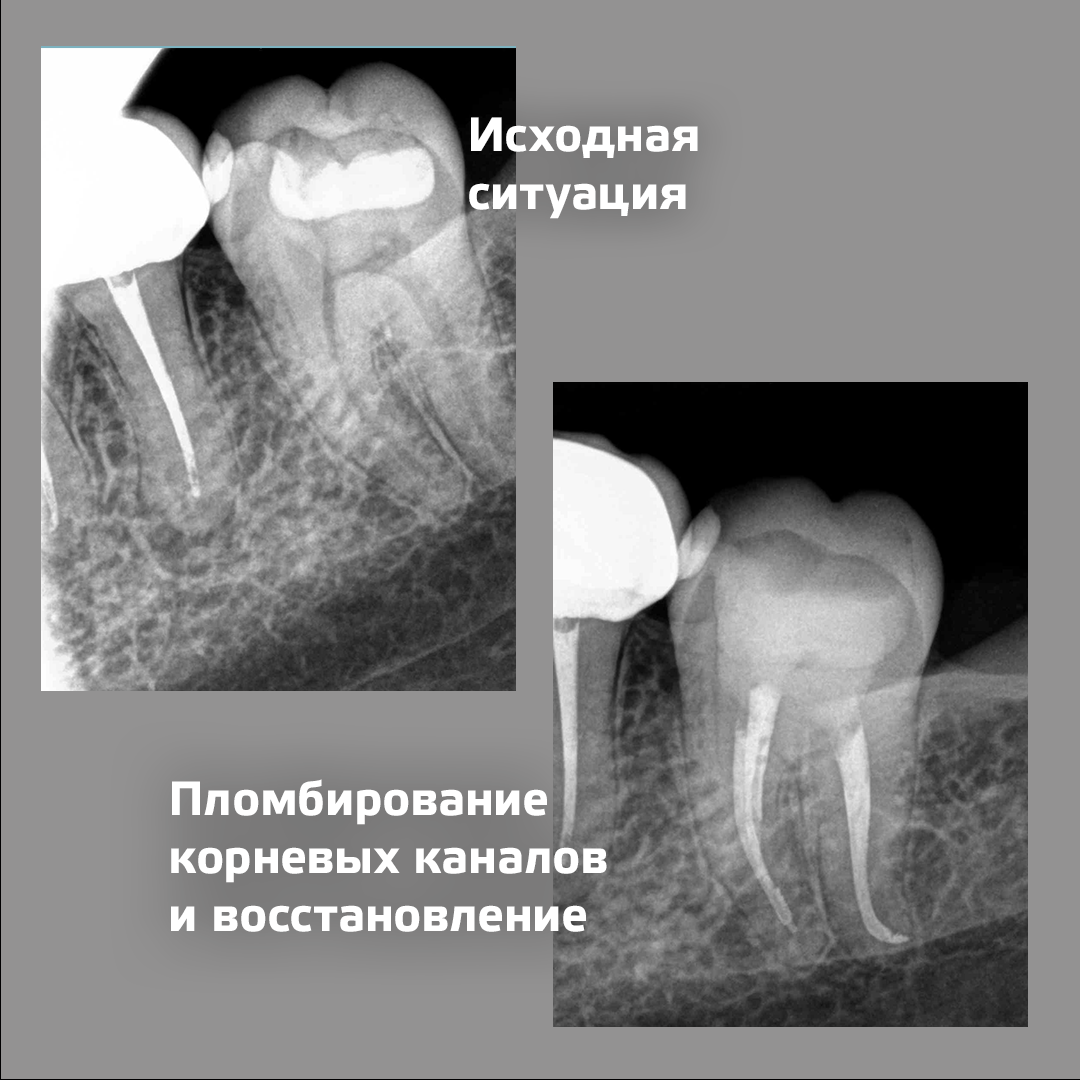

Тревожным симптомом для пациента стала характерная зубная боль, которая приходила в ночное время. Он обратился в клинику Киостом, и обследование показало, что 37-й зуб уже лечился ранее, когда-то там был глубокий кариозный процесс. Прошло время, и ситуация вновь потребовала внимания профессионала.

Стоматолог-эндодонтист клиники Киостом Никита Алексеевич Анисимов за одно посещение:

- раскрыл полость зуба

- произвёл инструментальную и медикаментозную обработку с последующим пломбированиям корневых каналов

- восстановил зуб пломбой.

В дальнейшем врач рекомендовал пациенту установить на вылеченный зуб коронку, чтобы качественнее укрепить его, тем самым зуб будет дольше служить пациенту.